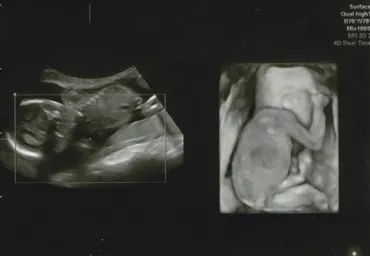

お腹の赤ちゃんをリアルタイムで観察できる4Dエコー検査。2Dエコーで体の断面をチェックした後、3D・4Dで赤ちゃんの立体的な姿や表情を動画で楽しめます。妊娠17~34週頃がおすすめ!親子の絆を深める感動体験を。ただし、詳細な診断には2Dエコーとの併用が重要です。検査方法や料金は病院によって異なるので、事前に確認しましょう!

2D、3D、4Dエコーなど、様々な種類があります。

✅ エコー写真は、妊婦健診で行われる超音波検査の結果を映し出したもので、2D、3D、4Dエコーなどの種類があります。

✅ エコーには様々な種類があり、3Dや4Dエコーでは赤ちゃんの表情や動きをより詳しく確認することができます。